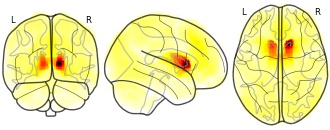

- N

pnajdz's temporary collection: R Anterior Caudate 12_16_8

EmailClick to copy linkLink copied Cite(2019). pnajdz's temporary collection: R Anterior Caudate 12_16_8 [Dataset]. http://identifiers.org/neurovault.image:295050Unique identifierhttps://identifiers.org/neurovault.image:295050Dataset updatedOct 3, 2019License

Cite(2019). pnajdz's temporary collection: R Anterior Caudate 12_16_8 [Dataset]. http://identifiers.org/neurovault.image:295050Unique identifierhttps://identifiers.org/neurovault.image:295050Dataset updatedOct 3, 2019LicenseCC0 1.0 Universal Public Domain Dedicationhttps://creativecommons.org/publicdomain/zero/1.0/

License information was derived automaticallyDescriptionCollection description

None

Subject species

homo sapiens

Modality

fMRI-BOLD

Cognitive paradigm (task)

rest eyes open

Map type

Z